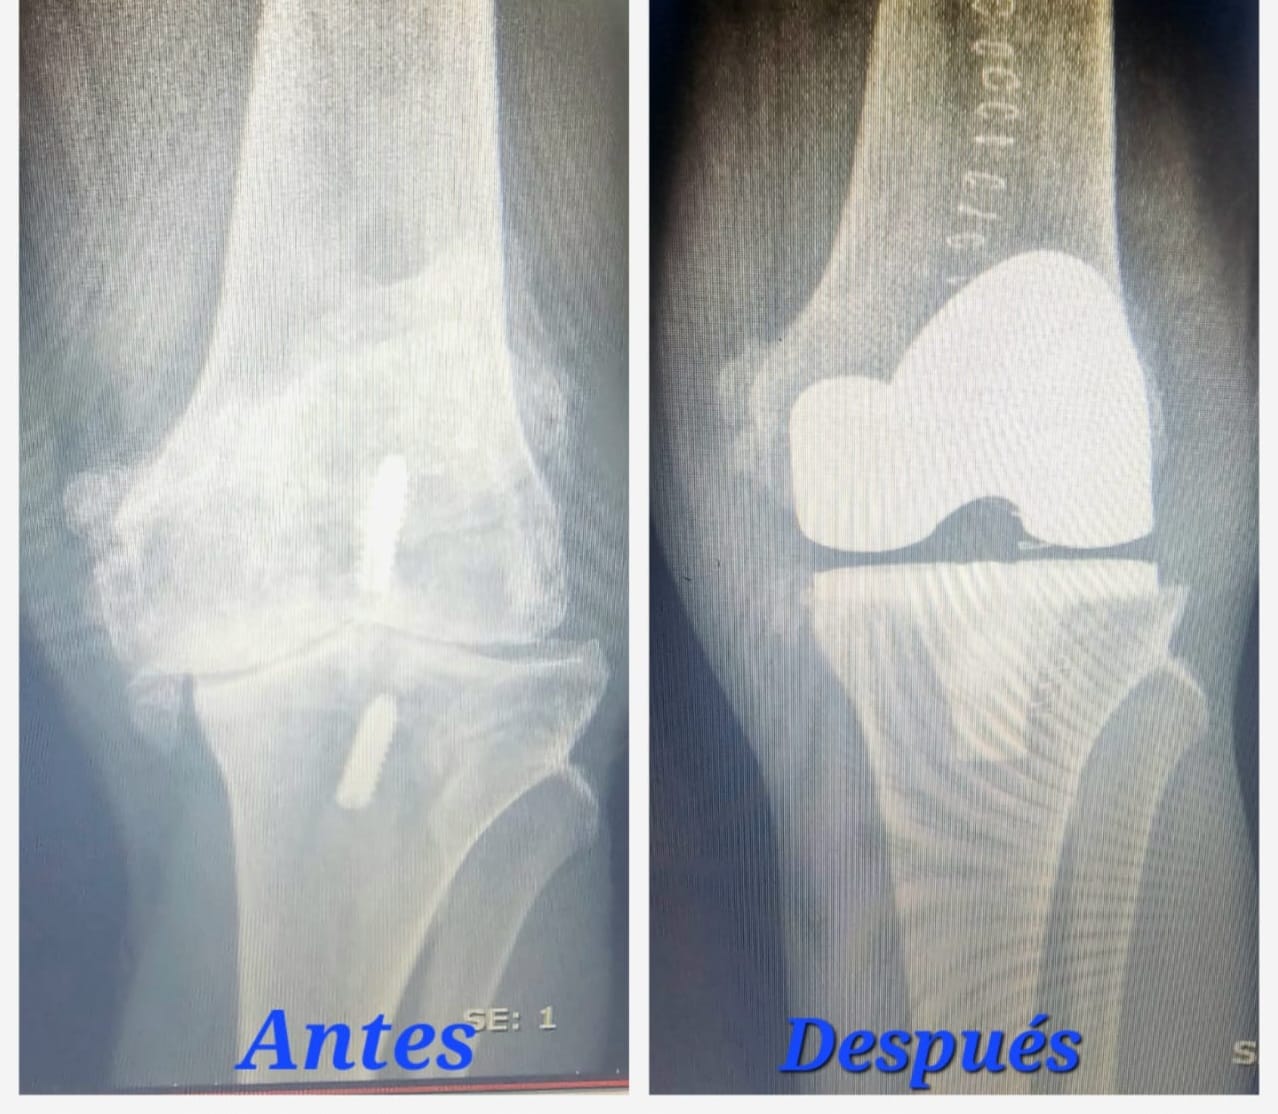

CORRECCIÓN DE AFLOJAMIENTO DE PRÓTESIS 1.PRÓTESIS AFLOJAMIENTO E INFECCIÓN DE VARIOS AÑOS. 2. RETIRO DE LA PRÓTESIS Y COLOCACIÓN DE PERLAS DE ANTIBIÓTICO ENTREVISTA PROGRAMA VIDA ENTREVISTA BDP CANAL 5 ENTREVISTA PIE PLANO ENTREVISTA ZAPATOS CORRECTOS INFILTRACIÓN DE ÁCIDO HYALURONICO EN CADERA